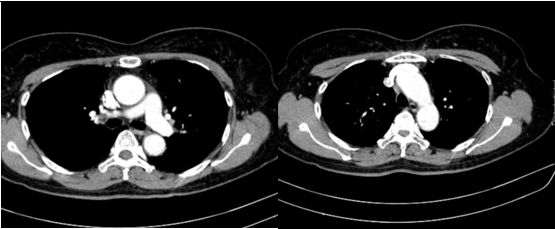

Hình 4:

Hình ảnh cắt lớp vi tính ổ bụng có tiêm: chưa phát hiện tổn thương nghi ngờ thứ phát

- Cắt lớp vi tính ổ bụng: Không phát hiện tổn thương bất thường.